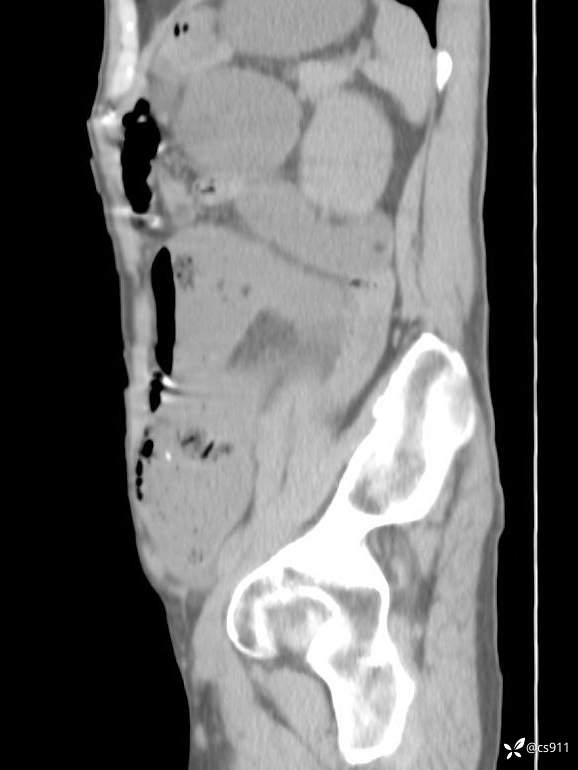

急腹症之急诊CT,原因?答案公布

男,77岁,腹痛、腹胀伴恶心呕吐1天。呕吐胃内容物,非喷射性呕吐,有咖啡色样胃内容物,诉有胃穿孔病史。查体:全腹平,下腹部压痛,全腹无反跳痛,叩诊呈浊音,移动性浊音阴性,肠鸣音减弱,1-2次/分。肛检:直肠未扪及明显肿物,可触及大量粪块。

T 36.6℃ P 80次/分 R 26次/分 BP 100/60mmHg

白细胞(WBC) H 14.55 10e9/L 4-10

红细胞(RBC) 4.58 10e12/L 4.3-5.8

中性粒细胞百分率(NEUT%) H 85.7 % 40-75

血淀粉酶(AMY) HH 1859 U/L 35-135

癌胚抗原(CEA) H 27.44 ng/ml 0-5

呕吐物 潜血试验 * 阳性 阴性

患者轮椅入室检查神志清楚, 能配合摆位和呼吸